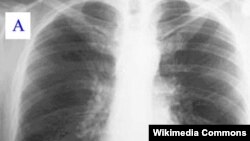

غربالگری سرطان ریه در حال حاضر بر اساس سن (۵۵ تا ۸۰ سال)، میزان مصرف سیگار افراد، و مدتی که از ترک سیگار می گذرد، بستگی دارد. این تیم پژوهشی با در نظر گرفتن «مدل های پیش بینی خطر» مختلف که به رفتارهای یک فرد، سبک زندگی، و تاریخچه خانوادگی بستگی دارد، درصد احتمال ابتلا و مرگ از سرطان ریه را پیش بینی کردند.